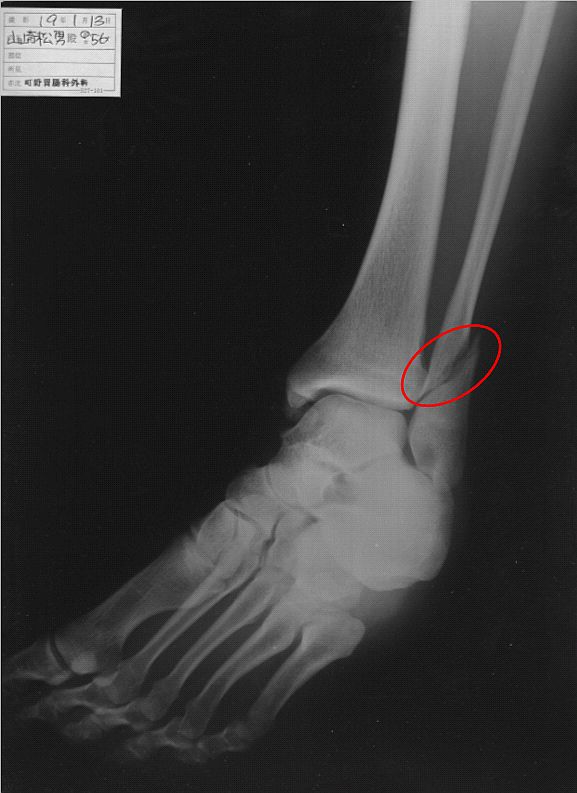

2007年1月10日左足間接外果骨折

骨折2日後のレントゲン